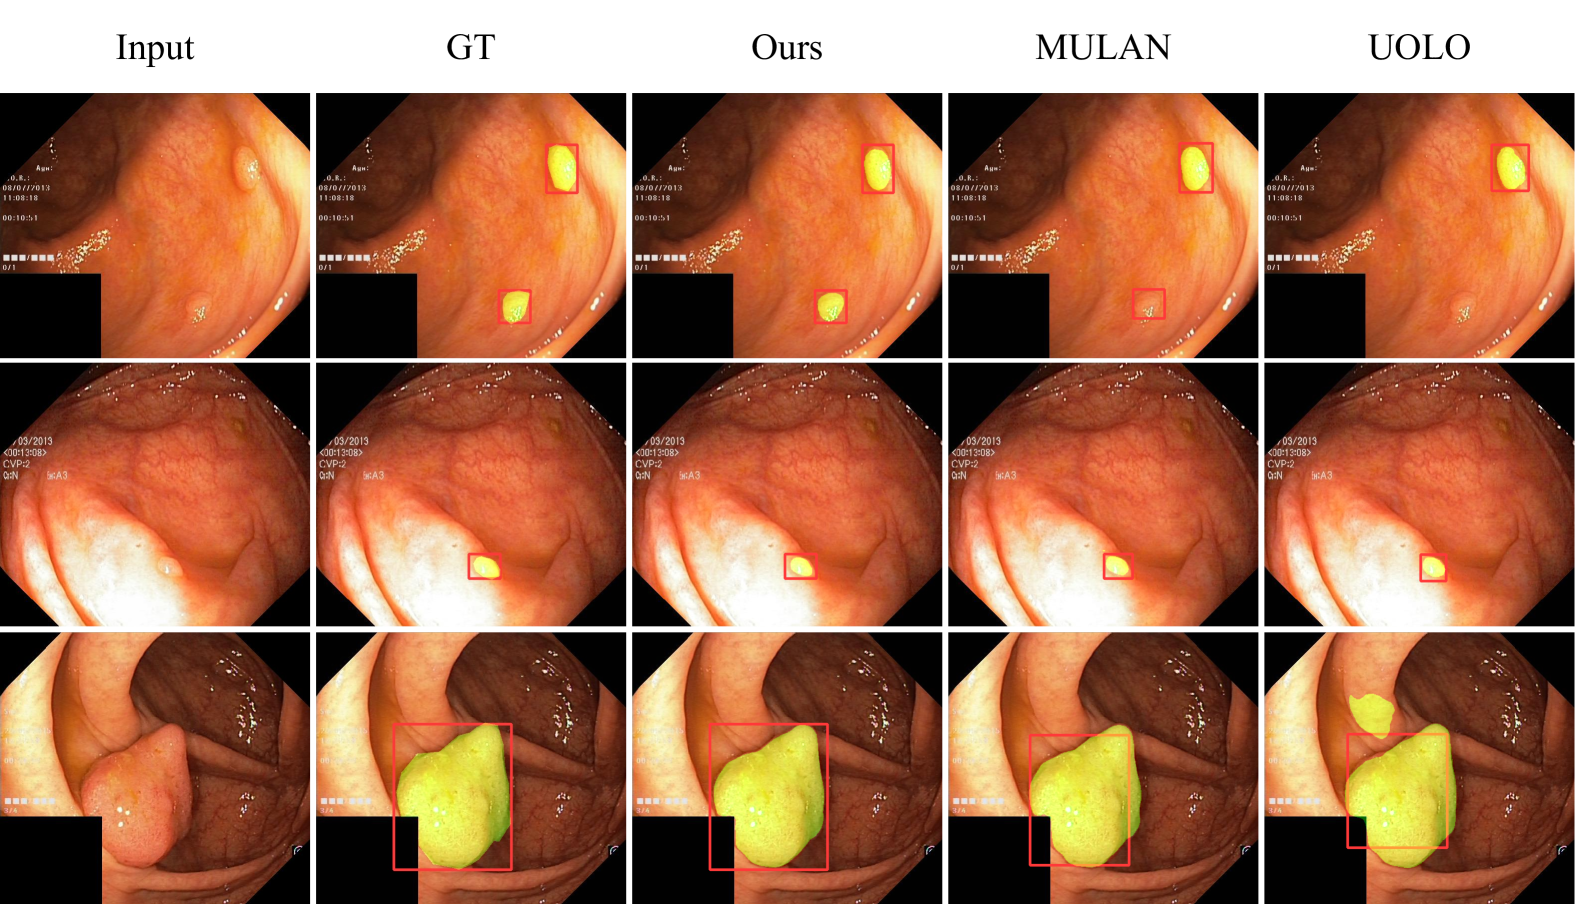

As depicted in Fig. 4, we conduct a qualitative performance analysis by comparing our network with UOLO [16] and MULAN [17] on Kvasir-seg [21]. Our network produces more accurate predictions for detection and segmentation, whether it involves multiple small objects (top), single small object (middle) and single huge object (bottom).

Refer to caption

Fig. 4: Qualitative comparison with two multi-task networks MULAN [17] and UOLO [16] on Kvasir-seg [21]. The detection and segmentation results are shown in the same figure.